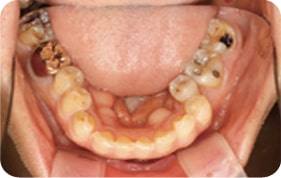

Case 1

2017. 07. 28

2017. 12. 05

2018. 03. 20

2018. 04. 28